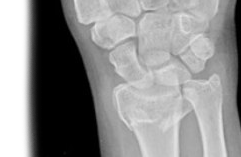

Рентгенография лучезапястного сустава – важный метод прицельного исследования, который позволяет оценить состояние лучезапястного сустава. Диагностическая услуга выполняется в двух проекциях.

Рентген позволяет исключить патологию лучезапястного сустава костно-травматического, дегенеративно-дистрофического, опухолевого генеза.